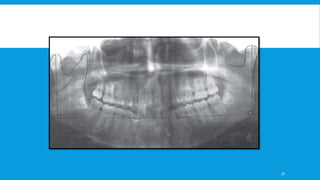

CONVENTIONAL RADIOGRAPHY

A. Orthopantomogram and lateral oblique View of mandible

–

 Either of these two views will give information on the overall relationship of proximal

and distal fragments in the antero-posterior plane.

 Sagittal displacement can be determined with a panoramic radiograph.

 The orthopantomogram has now become the more standard view providing, as it does,

an all-in-one view of the mandible.

 It is useful to supplement the standard view with a high OPG centred on the condyles

and this is best taken in the mouth open position if the patient is able to move the lower

jaw to any significant degree.

To evaluate the loss of ramus height,18,23,25 a panoramic radiograph is used.

The measurement technique is as follows -

• Line drawn between gonial angles across Panorex

• Perpendicular lines to most superior aspect of condylar heads

• The difference between the nonfractured and fractured side equals the

change in ramus height.